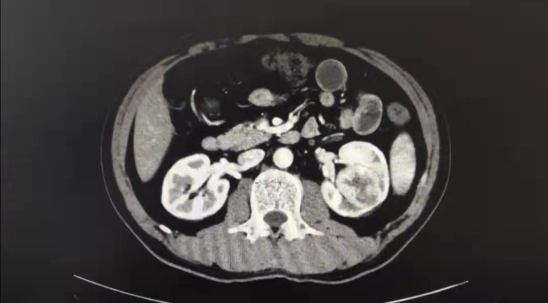

刘赞介绍,此肿瘤大于四公分,属于T1b肾肿瘤,呈完全内生性生长。整个肾的表面都是正常的,肿瘤就像“地雷”长在肾脏芯部,同肾盂、肾门血管关系密切,同时肾脏只能短暂的阻断血供。要保留肾脏,手术过程必须争分夺秒,在有限的血管临时阻断时间内,像拆雷一样,仔细完整地把肾脏里面的“地雷”小心的分离、取出,再缝合肾脏切口与重建肾盂,所以微创腔镜下手术难度非常大。